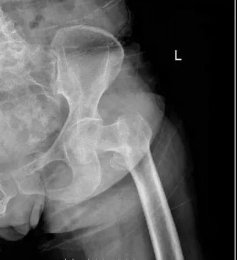

【案例分享】老年股骨轉(zhuǎn)子間骨折治療新選擇——人工髖關(guān)節(jié)置換 日期:2021-03-18 07:59:19 點(diǎn)擊:1922 好評:44

骨二科成功救治高齡老人右股骨轉(zhuǎn)子間骨折 濰坊市市立醫(yī)院骨二科近日為一位82歲高齡老人開展了老年股骨轉(zhuǎn)子間骨折患者的人工全髖或半髖關(guān)節(jié)置換手術(shù),取得良好的治療效果。王奶奶2月5日入院后被診斷為右股骨...